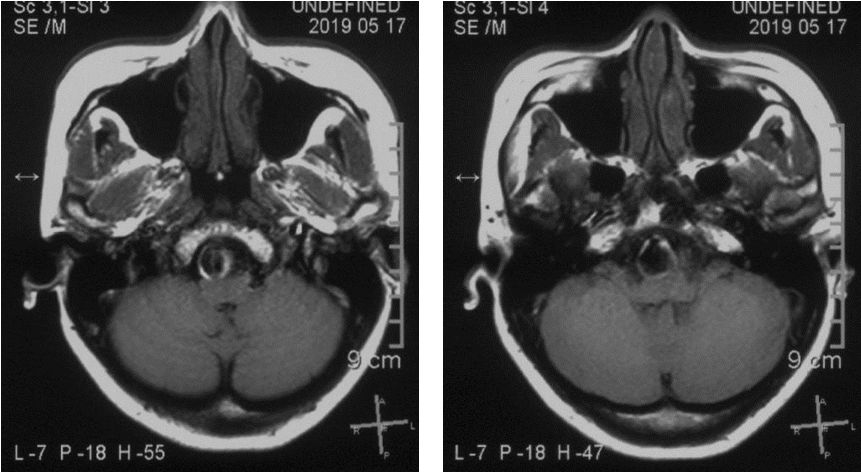

2019.5.17外院头颅MR

患者核磁共振显示脑桥-延髓前方流空影,考虑动脉瘤,有明显的双腔征,瘤壁有加强,且对脑干有一定的压迫。